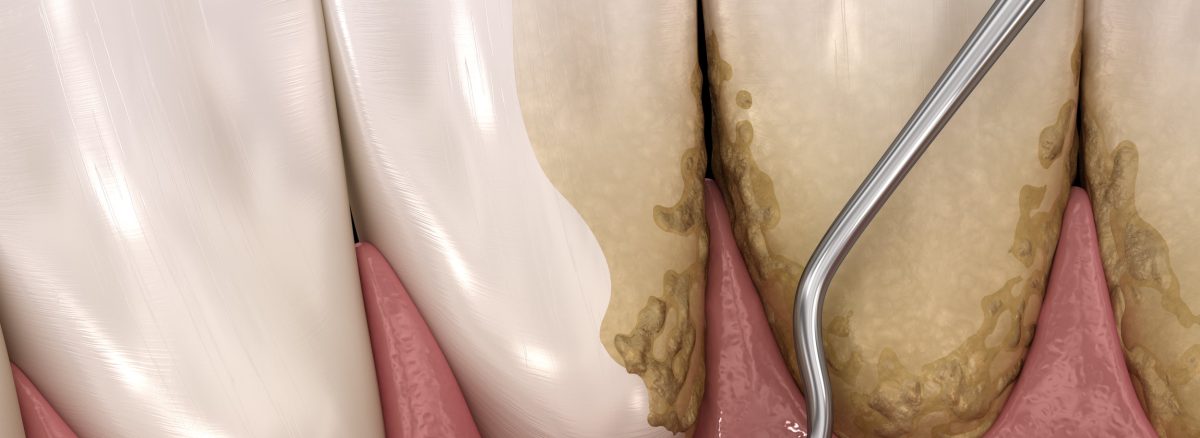

جرمگیری دندان (Scaling) یکی از روشهای درمانی در زمینه بهداشت دهان و دندان است که با استفاده از ابزارها و وسایل خاص، بافتهای نرم و سخت (پلاک و سنگ زدگی) را از سطح دندانها و لثهها پاکسازی میکند.این روش عمدتاً توسط دندانپزشکان یا بهداشت دهان کاران انجام میشود و میتواند به عنوان یکی از مراحل درمان برخی بیماریهای لثه و زیباییدهی دندانها استفاده شود.

- جرمگیری: با استفاده از ابزارهای ویژه شامل جرمگیرها و اسکیلرها، پلاک و سنگ زدگی روی سطح دندانها و در برخی موارد روی ریشه دندانها به دقت پاکسازی میشود. این عملیات میتواند با یک سری ابزار دستی یا با استفاده از دستگاههای اولتراسونیک صورت بگیرد.

بعد از آمادهسازی، دندانپزشک با استفاده از ابزارهای ویژه، شامل جرمگیرها و اسکیلرها، پلاک و سنگ زدگی روی سطح دندانها و در صورت لزوم روی ریشه دندانها را پاکسازی میکند. به طور معمول، از جرمگیرهای دستی و یا دستگاههای اولتراسونیک برای این منظور استفاده میشود. در این مرحله، بافتهای نرم و سختی که روی سطح دندان وجود دارد، پاکسازی میشود.